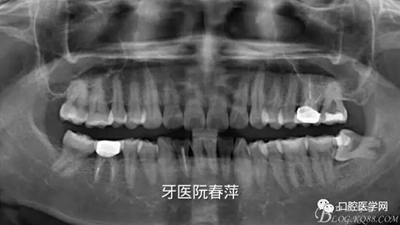

戴牙后全景片:

【X光片檢查】

后牙的修復(fù)體X光線阻射應(yīng)該強于釉質(zhì),以方便日后對繼發(fā)齲的檢查。X光片還能從直觀上對修復(fù)體邊緣是否密貼,鄰面有無懸突進行進一步的檢查。